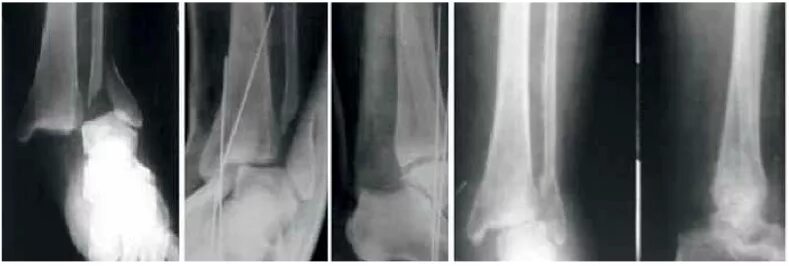

Доа голеностопного сустава мкб